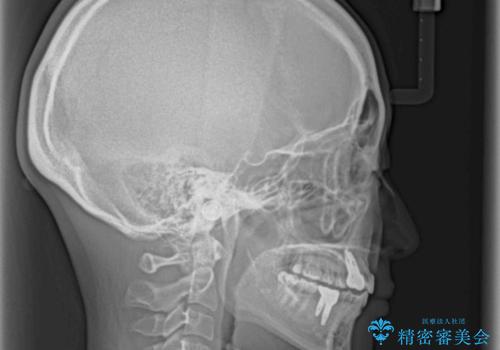

欠損と残存乳歯 矯正治療とインプラント治療

- 残存した乳歯や歯の欠損、歯並びを気にして来院された患者様です。

乳歯を残した状態は予後がよくないこと、矯正治療と補綴治療を総合的に進めていきたいとのことで、インビザラインによる矯正治療とインプラント補綴治療を並行して進めていくこととしました。

当院は矯正治療もインプラント補綴治療も、同一の歯科医師が担当するため、矯正治療を行いながら、最適なタイミングでインプラント補綴治療を行うことが可能です。